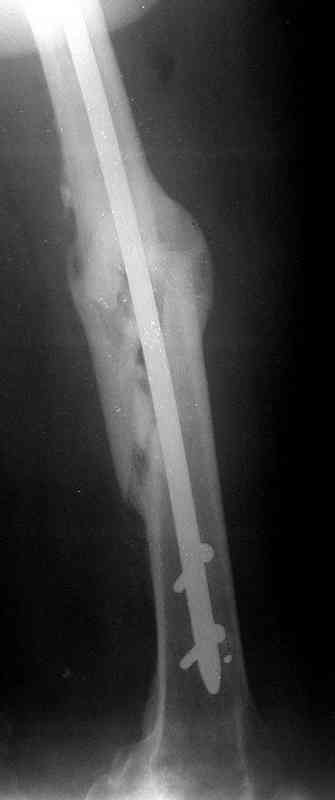

по его наружной поверхности послеоперационный рубец - рана зажила первичным натяжением. При измерении длины бедер обнаружено укорочение левого бедра на 4,5 см. На рентгенограммах этого бедра: ось конечности правильная, отмечается захождение основных костных фрагментов по длине, проксимальный конец штифта выступает слишком медиально и высоко относительно большого вертела, периостальная мозоль незначительна.22.12 - через 6 месяцев после операции, произведенной в ЦРБ, нами по поводу замедленно консолидирующего перелома левой бедренной кости с ее абсолютным укорочением под наркозом произведена операция: удаление штифта, закрытый блокирующий интрамедуллярный остеосинтез перелома левого бедра штифтом без рассверливания (UFN) длиной 40 см, диаметром 10 мм с блокированием только проксимальных отверстий (динамический остеосинтез). Наложен аппарат Илизарова на 4 полукольцах с целью удлинения укороченного бедра. Послеоперационное течение без особенностей. Ежедневно осуществляли дистракцию отломков на 1 мм. Через 3 недели после операции больной выпи-сан на амбулаторное лечение с продолжением дистракции отломков. В течение 1,5

месяцев дистракции укорочение левого бедра удалось полностью устранить. 22.02.00, т.е. через 2 месяца после повторного остеосинтеза, больному произведено дистальное блокирование штифта двумя винтами и демонтирован аппарат Илизарова. В течение 2 недель после операции больной ходил с помощью костылей, потом 2 недели с тростью. Опороспособность и функция оперированной конечности полностью восстановились через 4 недели после операции.

Фиксаторы удалены через 12 месяцев после операции, выполненной по поводу замедленной консолидации перелома бедра с его укорочением.